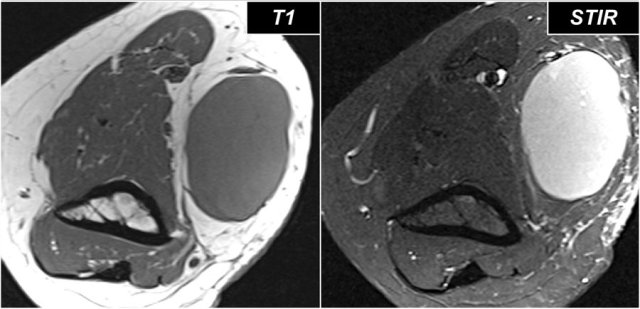

Denervation

Nerve pathology can present as thickening of the nerve when there is neuritis or as a result of compression of the nerve.

A secondary sign of nerve pathology is denervationwith edema and/or atrophy of the muscle.

In this case there is chronic atrophy with high sinal on T1, which is irreversible.

In early or subacute denervation the prominent sign is edema with high signal on T2W-images and that is reversible.

This is a 48 year old male with Marfan's syndrome, who had a sudden onset of right hand weakness.

This is a nice example of subacute denervation.

Notice on the T1W-image that there is no atrophy.

Only edema on the T2W-image.

This was due to proximal radial neuropathy.